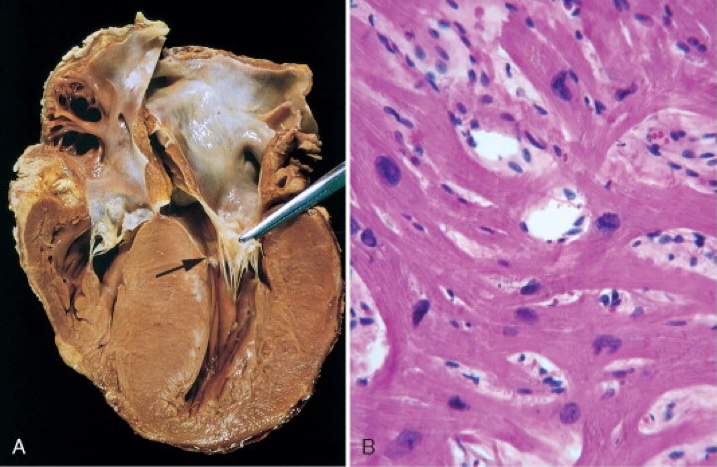

Hypertrophic Cardiomyopathy (HOCM)

- Pathogenesis:

- Myocardial hypertrophy (especially septal) → diastolic dysfunction

- May result in left ventricular outflow tract (LVOT) obstruction

- Investigations:

- Echo: Asymmetric septal hypertrophy, diastolic dysfunction